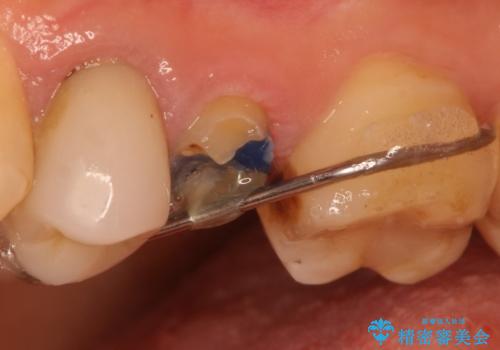

過去に治療してあった左上の歯が一部欠けていました。

かぶせ物と詰めてある修復物を除去すると歯肉の中まで虫歯になっていました。